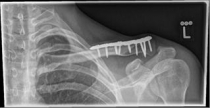

Images: A lateral clavicle fracture was treated with a hook plate. The hook is fixed under the acromioclavicular, while screws anchor the plate in the collarbone.